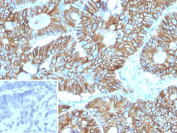

It recognizes a glycosylated protein of 120kDa, which is identified as Cadherin 17 (also known as LI Cadherin). The cadherins are a family of Calcium-dependent adhesion molecules that function to mediate cell-cell binding critical to the maintenance of tissue structure and morphogenesis. Cadherins each contain a large extracellular domain at the amino terminus, which is characterized by a series of five homologous repeats, the most distal of which is thought to be responsible for binding specificity. The relatively short carboxy terminal, intracellular domain interacts with a variety of cytoplasmic proteins, including beta-catenin, to regulate cadherin function. LI-cadherin (for liver-intestine-cadherin) expression is restricted to liver and intestine tissues and is specifically localized to the basolateral domain of hepatocytes and enterocytes.

A recombinant human partial protein (amino acids 242-418) was used as the immunogen for the Cadherin 17 antibody.